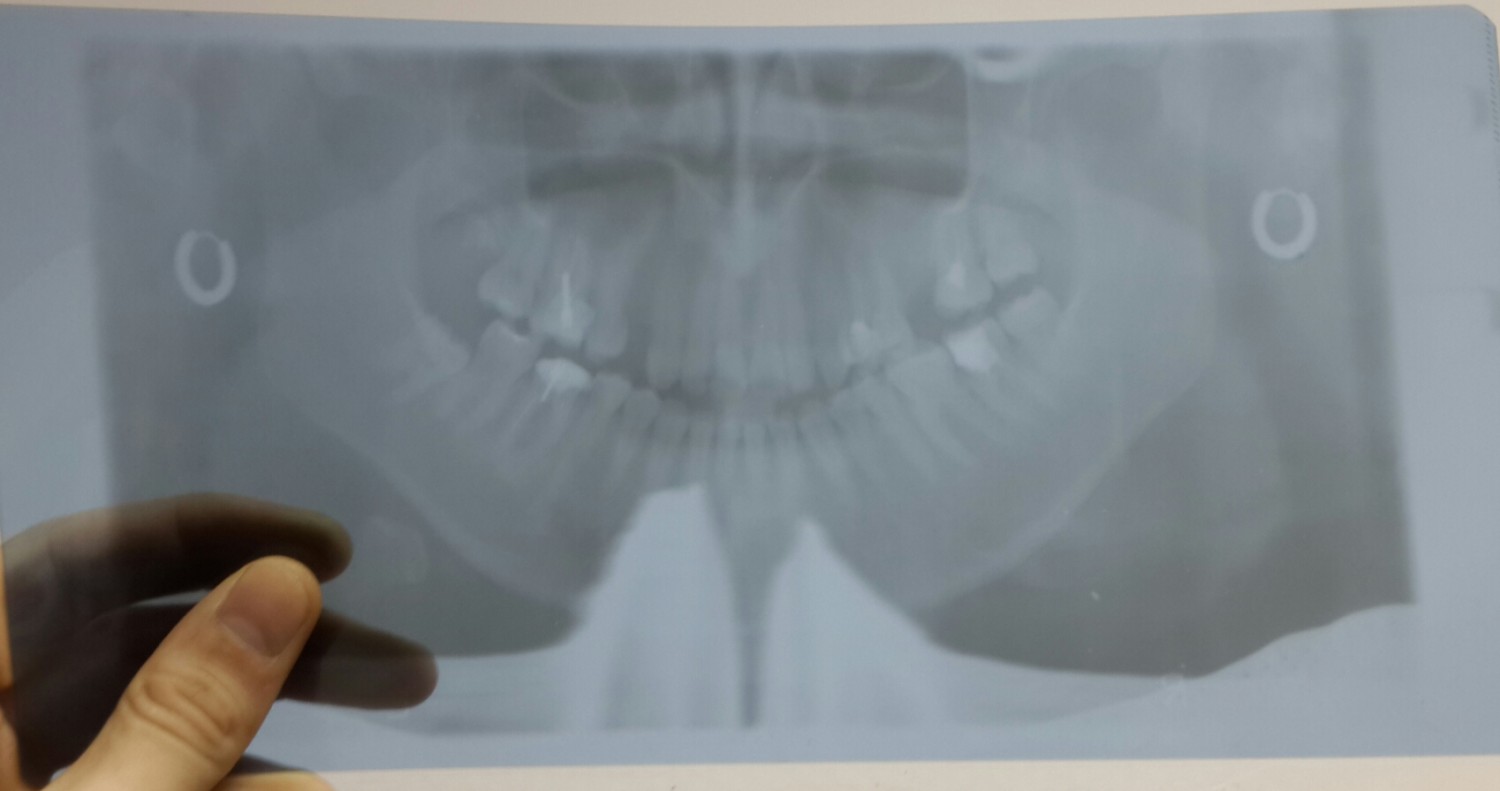

снимки стали онформативны, но на программе 11, при 1,3-кратном увеличении рамки вообще по 3,5 см. и сам снимок аналогичен 1 программе, только "обгрыз" края. может у кого-нибудь есть какие нибудь мысли, поделитесь пожалуйста.

8772354.jpg (78.0 Kb) · 3303867.jpg (92.7 Kb)

Ты хочешь получить на этом снимке и шейный отдел?

Снимки замечательные, пропорции не нарушены, что еще нужно? Если сомневаешься, поставь туда голову и проследи

путь луча в крайних точках, все станет на свои места.